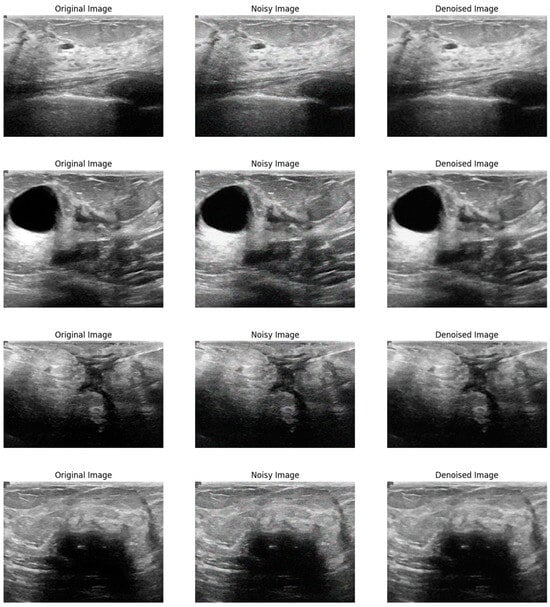

Figure 2 illustrates the visual effectiveness of the proposed denoising method. The figure displays three images for comparison: the original noise-free image, the image corrupted by Gaussian noise, and the image after being denoised using the proposed method. This visual comparison provides a qualitative assessment of the denoising performance, supplementing the quantitative results discussed earlier. The original image serves as a reference, showing the image without any noise interference. The noisy image, corrupted by Gaussian noise, exhibits significant visual distortions that obscure finer details and compromise the visibility of important structural information. In contrast, the denoised image produced by the proposed method shows a remarkable reduction in noise levels, with enhanced clarity and preservation of structural details. This comparison clearly demonstrates the ability of the proposed method to effectively remove noise while maintaining the quality and integrity of the original image.

Figure 2.

Visual comparison of the proposed method on Gaussian noise.

Figure 3 shows a visual comparison of the original image, the image corrupted by Poisson noise, and the denoised image produced using the proposed method. The original image serves as a baseline, displaying clear and noise-free content. The second image illustrates the significant noise introduced by Poisson distortion, which impacts image clarity and detail. In contrast, the final image demonstrates the effectiveness of the proposed denoising method, showing a substantial reduction in noise and an enhancement in image quality while preserving critical details. This comparison highlights the ability of the proposed method to effectively restore the image and mitigate the adverse effects of Poisson noise.

Figure 3.

Visual comparison of the proposed method on Poisson noise.